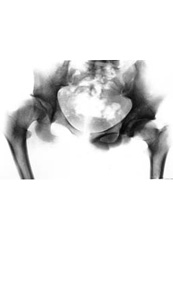

Result of the treatment.

Full flexion of knee-joints.